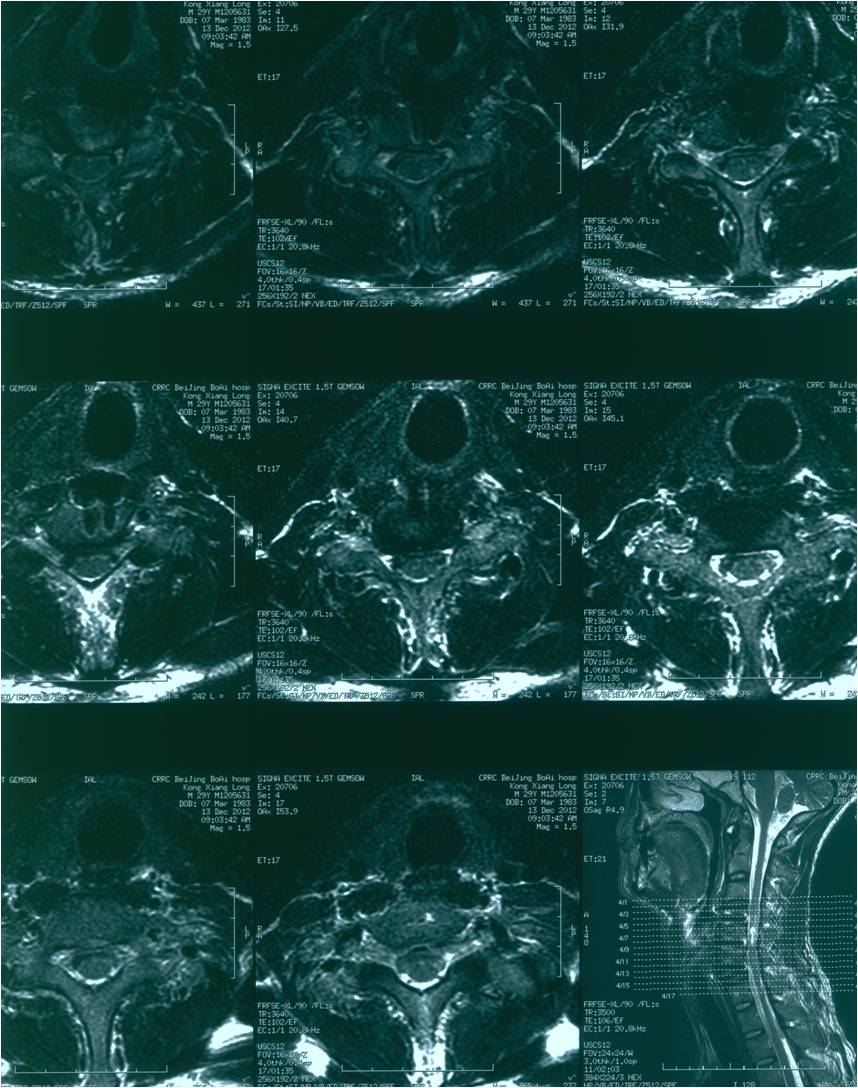

2012-11-18 车祸致四肢感觉、运动及二便功能障碍。

查体:意识清楚,呼吸均匀,查体合作。双侧感觉平面颈4,运动平面颈5. 颈6以下轻触觉保留至肛周,针刺觉消失。颈5以下只有肛门括约肌保留运动功能。下肢肌张力0级。腱反射消失。球海绵体反射可引出。当地医院行X片、CT、MRI检查